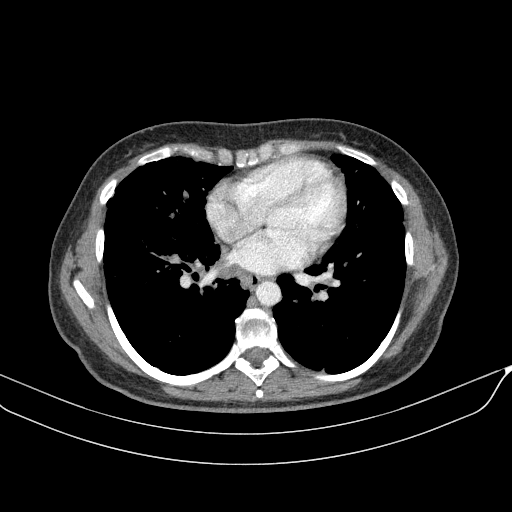

Image Grid

4Γ—3 grid: Rows show different image types (Original NATIVE, Reconstructed NATIVE, Original VENOUS, Generated VENOUS), Columns show windowing techniques (No Window, Lung Window, Mediastinum Window)

Generated VENOUS CT scan (A→B translation)

Full window (WL 1023.5, WW 4095 β†’ Low βˆ’1024, High +3071)

Reconstructed NATIVE CT scan (cycle consistency)